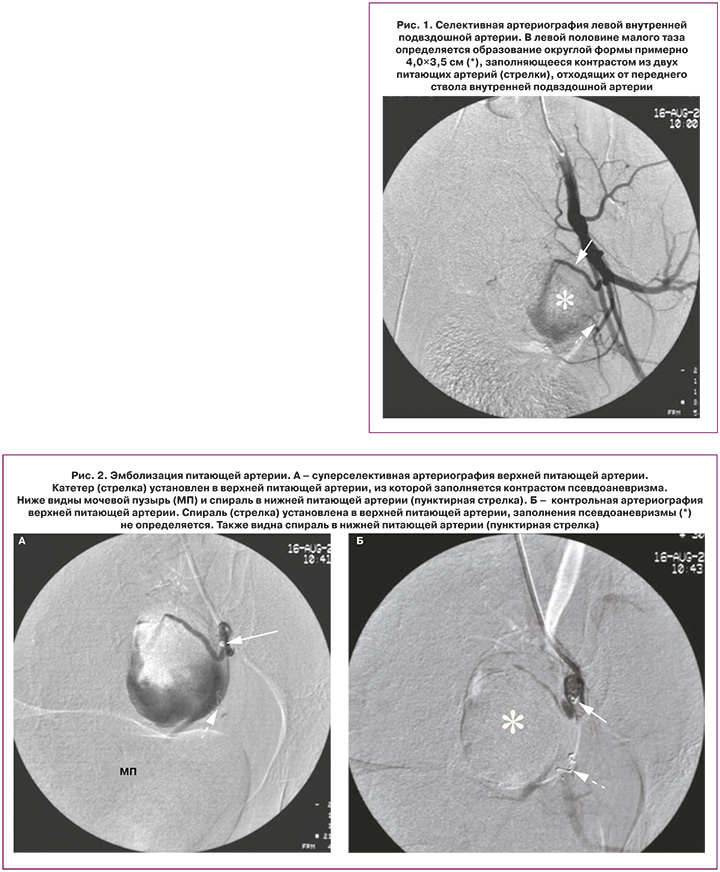

Учитывая клинико-инструментальные данные, решено провести ангиографию сосудов малого таза и при необходимости – эмболизацию патологического образования. На 6-е сутки после операции в 09.00 экстренно выполнена ангиография сосудов таза с последующей эмболизацией ветвей, питающих псевдоаневризму. Под местной анестезией 20 мл 0,5% раствора новокаина пунктирована правая общая бедренная артерия, введен интродьюсер 5 F, через него в брюшную аорту введен катетер JR 4.0 5 F. Он установлен в устье левой общей подвздошной артерии. При артериографии с ручным контрастированием 60% урографином выявлено объемное образование 40×35 мм (*) в проекции матки слева с активным заполнением из ветви внутренней подвздошной артерии.

При селективном контрастировании из левой внутренней подвздошной артерии определяются две питающие образование (*) артерии (стрелки) (рис. 1). Суперселективно катетер проведен в нижнюю питающую артерию, имплантирована спираль IMWCE-35-3-5 («Cook Medical»). Затем катетер установлен суперселективно в верхней питающей артерии, при артериографии заполняется только псевдоаневризма (рис. 2а). В полость аневризмы введено 100 мг частиц поливинилалкоголя размером 500 мк («Cook Medical»), однако снижения кровотока и тромбирования аневризмы не последовало. Имплантирована спираль IMWCE-35-3-5 («Cook Medical»). При артериографии питающей артерии через 3 минуты псевдоаневризма не заполняется (рис. 2б). При артериографии левой общей подвздошной артерии с ручным контрастированием объемное образование (*) в проекции матки слева не контрастируется (рис. 3). Также выполнена артериография правой общей подвздошной артерии с ручным контрастированием – данных за контрастирование аневризмы из ветвей внутренней подвздошной артерии не получено. Катетер и интродьюсер извлечены, гемостаз области катетеризации 10 мин. Давящая повязка.